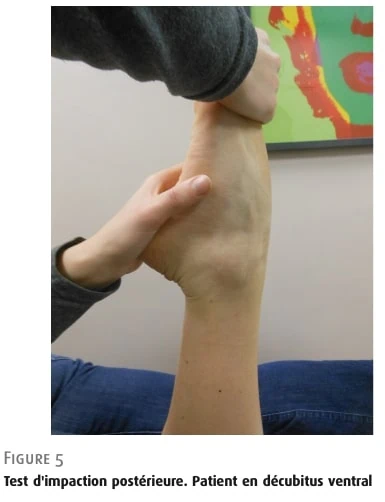

- 后踝关节撞击试验。

根据研究报告的作者,这项检测更能说明骨性撞击的征兆。 如果试验阳性可再现患者的症状,并可使用两种不同的技术进行试验,则该试验被视为阳性:

坐位患者: 患者坐在检查台边,双腿悬空,膝关节屈曲 90°。 检查者用力跖屈足部,另一只手稳定足跟。

俯卧病人: 患者俯卧,膝关节屈曲 90°,脚以同样方式移至跖屈位(图 5)。

图 5 后撞击试验。 患者俯卧姿势。